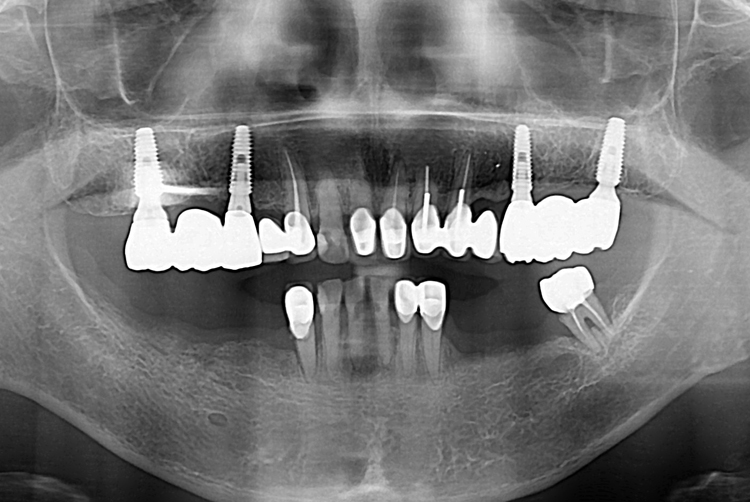

[임플란트] 어금니 임플란트

치료후 : 2017-12-28

세종치과는 많은 환자와 다양한 케이스를 바탕으로

항상 편안한 임플란트 수술을 제공하고자 노력하고,

오래동안 튼튼히 쓸 수 있는 임플란트 수술을 가장 큰 목표로 삼고 있습니다.